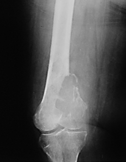

Dev Hücreli Kemik Tümörü

Kemiğin selim-agresif tümörü olarak kabul edilir. Genç erişkinde osteolitik karakterde kemik tümörüdür. Uzun kemiklerin ekleme yakın uç kısmından çıkabilir. Hastalar tümör bölgesinde devamlı ve giderek artan inatçı bir ağrı ve şişlik ile başvururlar.Sadece küretaj yapılan hastalarda yüksek lokal nüks yanında akciğer metastazı yapma potansiyeli olduğundan lokal agresif tümör olarak kabul edilir. Ama bu metastazlar ölümcül değildir.Diz eklemi en sık tutulan bölgedir. Diğer sık tutulan bölge el bileğidir. Kemik korteksini harap ederek yumuşak dokulara yayılım gösterebilir. Tanı için biyopsi şarttır. Brown tümörü ile ayırıcı tanısı yapılmalıdır. Tanı esnasında akciğer tomografisi çekilmelidir.

Tedavide genişletilmiş küretaj ve adjuvan ajanlarla kalan tümör hücreleri öldürülmeye çalışılır. Adjuvan ajan olarak; sıvı azot, alkol, fenol, argon koter, kriyoterapi, yüksek hızlı burr ve sementleme (kemik çimentosu) uygulanır. Eklemin tutulduğu vakalarda eklem feda edilir,protez veya artrodez uygulanabilir. Rezeksiyonun zor olduğu olgularda denosumab kullanılması önerilmektedir.Hastaların lokal nüks ihtimaline karşı 10 yıl süre ile takibi yapılmalıdır.